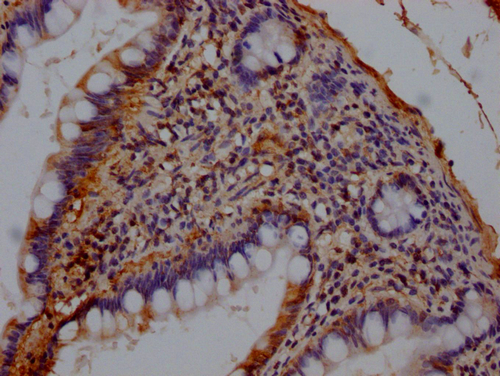

• IHC image of CSB-PA17772A0Rb diluted at 1:140 and staining in paraffin-embedded human small intestine tissue performed on a Leica BondTM system. After dewaxing and hydration, antigen retrieval was mediated by high pressure in a citrate buffer (pH 6.0). Section was blocked with 10% normal goat serum 30min at RT. Then primary antibody (1% BSA) was incubated at 4°C overnight. The primary is detected by a Goat anti-rabbit IgG labeled by HRP and visualized using 0.05% DAB.